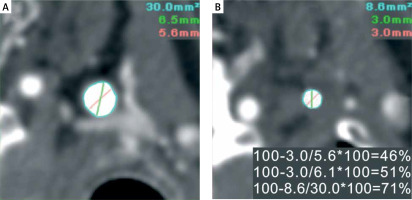

Figure 1

Principles of diameter stenosis-based and area stenosis-based quantification of carotid lumen reduction expressed as “percent stenosis” using computed tomography angiography (CTA). A 56-year-old neurologically asymptomatic office worker, whose brother-in-law experienced a disabling stroke in relation to atherosclerotic carotid stenosis, presented in a vascular surgery outpatient clinic with DUS examination indicating a border-line left internal carotid artery (LICA) lesion (PSV/EDV 2.1/0.6 m/s consistent with “50–69%” stenosis [11]). CTA request was made to increase the precision of stenosis severity determination and aid further decision-making [22–24]. By CTA, the LICA lumen was not fully circular in the reference plane (A), but there was a rather concentric lumen reduction in the minimal lumen area plane (B). Diameter stenosis (DS)-based calculations, depending on the use of minimal vs. average diameter in the reference plane, show stenosis of “46%” (when the minimal reference diameter is used) or “51%” (with average reference diameter use). Thus, according to diameter stenosis-based calculations, the threshold of “≥ 60% stenosis” was not crossed to consider revascularization of this neurologically asymptomatic lesion [3, 6]. In contrast, with the area reduction-based calculation (see the bottom measurement in panel B) the “percent stenosis” is “71%”, placing this patient in the stenosis severity cohort where revascularization may be performed to reduce stroke risk according to both European and North American guidelines [3, 6]. Surgical revascularization (CEA) could thus be performed, particularly in the case of a radiology report limited to the area-based calculation of stenosis severity, which is not infrequent [19]. It is common that in the case of both AS- and DS-derived calculations provided in the radiology report [19], the “more severe” measurement could be taken as the basis for the clinical decision. Note that carotid artery stenting or trans-carotid stent-assisted revascularization, with their inherent “final” confirmation of lesion severity by intra-arterial angiography (standard of reference), would probably have resulted in deferring any interventional management because in this study patient catheter quantitative angiography (cQA, NASCET method) revealed LICA stenosis severity of 47%. Medical therapy was maximized to reduce stroke risk [3, 25, 26], and the patient is monitored yearly in a certified DUS lab for potential stenosis progression [3, 4, 6] along with imaging and clinical observation for de novo presence of other increased stroke risk characteristics [3, 4, 6, 25, 26]. A documented increase in stenosis severity would trigger the NeuroVascular Team to re-consider recommended management, which would involve the patient’s opinion (based on complete information on treatment options [26]) in the decision-making process

PSV – peak systolic velocity, EDV – end diastolic velocity, CTA – computed tomography angiography, CEA – carotid endarterectomy, cQA – catheter (intra-arterial) quantitative angiography, NASCET – North American Symptomatic Carotid Endarterectomy Trial.